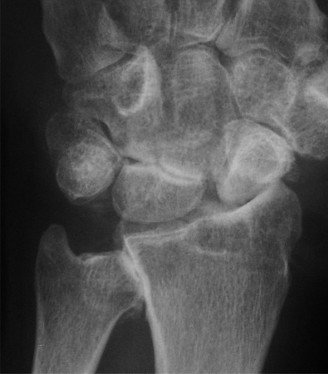

Standard posteroanterior (PA) and lateral radiographs of the wrist often fail to adequately visualize the pisotriquetral joint due to bony overlap from the distal pole of the scaphoid, the capitate, and the triquetrum itself. To properly assess this articulation, a 30-degree supinated AP view (the pisotriquetral view) is mandatory. In our first patient (referencing the classic Figure 3-10), this specific view reveals profound joint space narrowing, subchondral sclerosis, and prominent osteophyte formation at the pisotriquetral interface.

It is crucial to understand the osteology here. The pisiform is an atavistic, sesamoid bone. It is the only carpal bone that does not participate in the complex intercarpal kinematics of the proximal or distal rows. Instead, it lies entirely within the tendon of the flexor carpi ulnaris (FCU). The FCU-pisiform complex extends distally via robust ligamentous attachments: the pisotriquetral ligament, the pisohamate ligament, and the piso-5th metacarpal ligament. Notably, there is no piso-scaphoid ligament; the scaphoid resides on the entirely opposite side of the carpus.